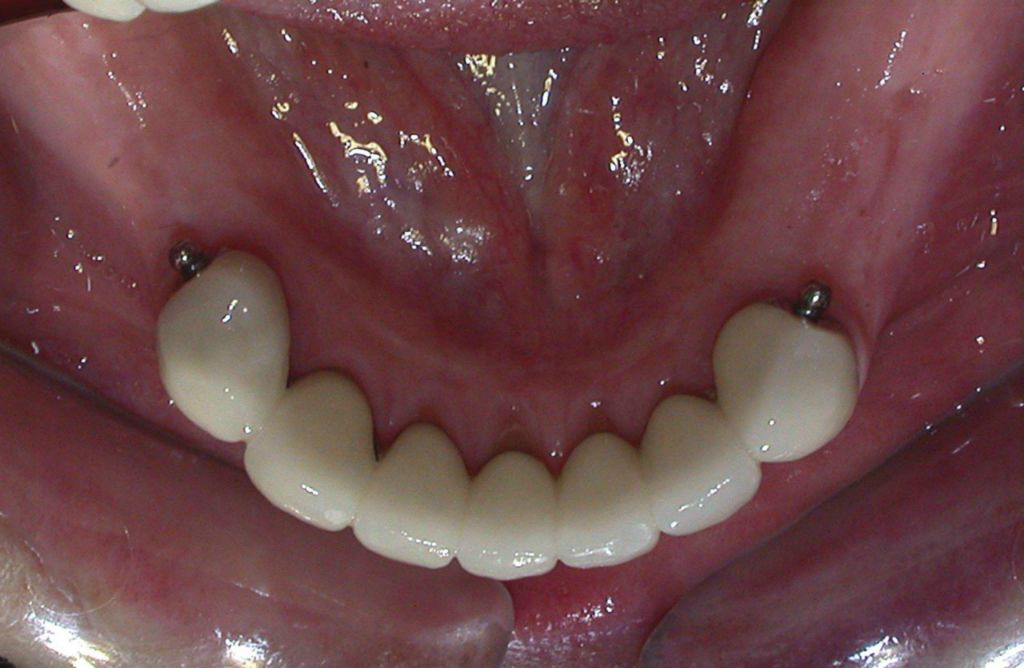

Zirconia bridge on Southern DC Implants